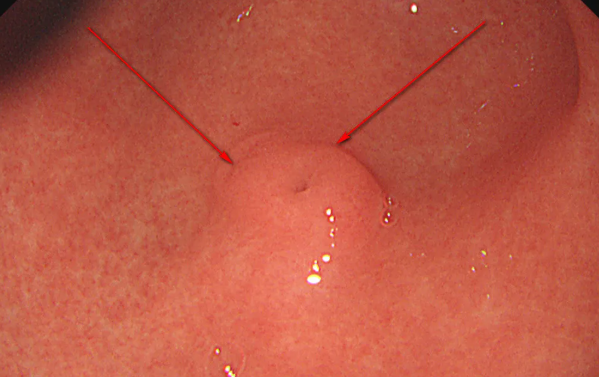

结肠息肉不用愁,日间手术来解忧!

2024-12-31

肠息肉是吃出来的吗?肠息肉摘除术后饮食指导

2024-09-30

肠息肉切除术后多久需要复查?

2024-05-09